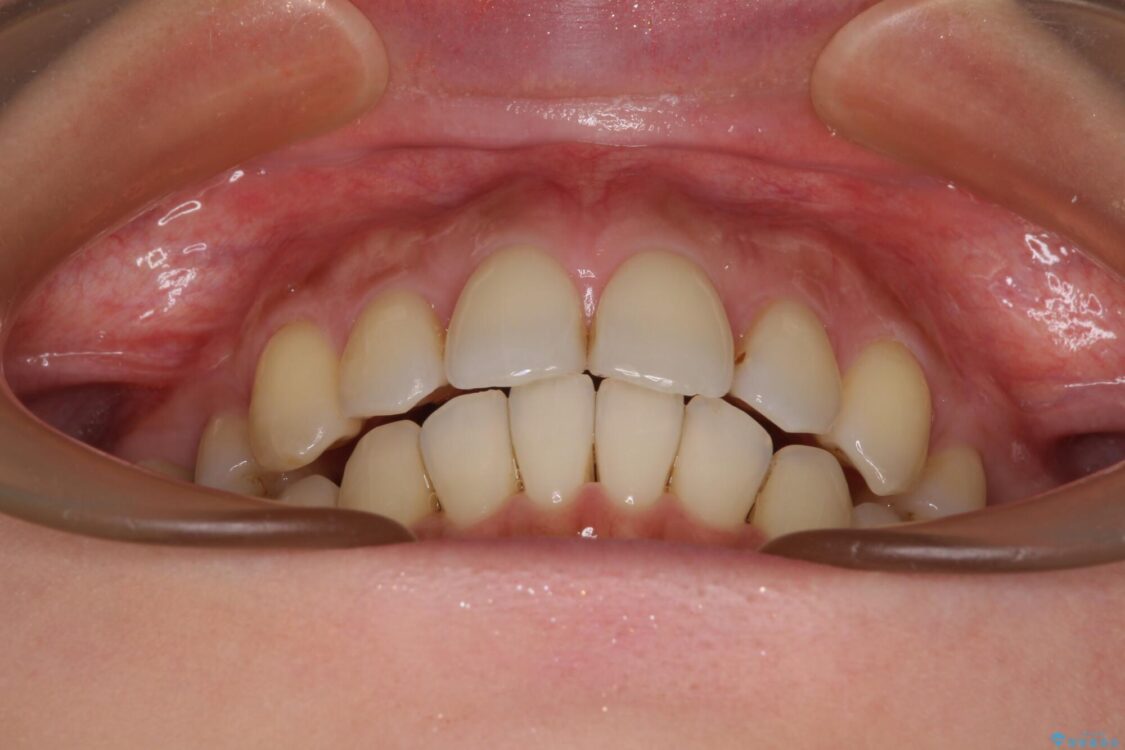

治療前

• 上顎前歯の突出を軽減 インビザラインによる抜歯矯正 治療前画像